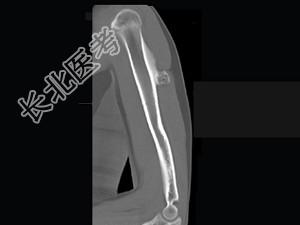

单项选择题男,28岁, 左手臂上部可扪及一硬结,有轻压痛, 结合图像,最可能的诊断是 ( )

A、骨软骨瘤

B、骨旁骨瘤

C、表面骨肉瘤

D、皮质旁软骨瘤

E、皮质旁软骨肉瘤